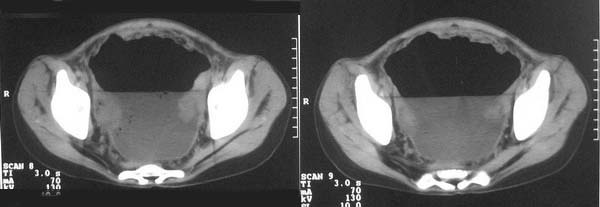

f-18y,腹痛,腹胀,停止排便排气4天,小便正常,四年前阑尾炎手术,病人已手术,明天上传结果。

直肠左侧低密度模糊影,乙状结肠明显扩张,有宽大液平,下腹部肠袢欠规整,内有多发小液平,结合有阑尾炎手术史考虑:直肠周围脓肿,低位肠梗阻,肠粘连。

盆腔巨大脓肿,据术者讲,脓肿大部分壁是有肠管壁形成的,少部分有自己较厚的壁,子宫、附件都泡在脓液里,腹腔肠管广泛粘连,这个病例奇怪的是急性发病,追问不出慢性病史。